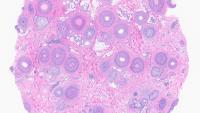

Take the first step towards a rewarding career in Dermatopathology by enrolling in Columbia University Irving Medical Center/NewYork Presbyterian Hospital's comprehensive one-year ACGME-accredited fellowship program. Tailored for graduates of Dermatology or Pathology residencies, this intensive program delves into diverse disciplines including immunopathology, molecular dermatopathology, and genomics.

Supported by a dynamic collaboration between Dermatology and Pathology & Cell Biology departments, fellows access unparalleled subspecialty clinics and contribute to cutting-edge research in a high-volume setting. Under the guidance of renowned faculty mentors, fellows engage in clinical, translational research, and educational initiatives, shaping the future of dermatopathology while honing their expertise through hands-on experience and scholarly pursuits.